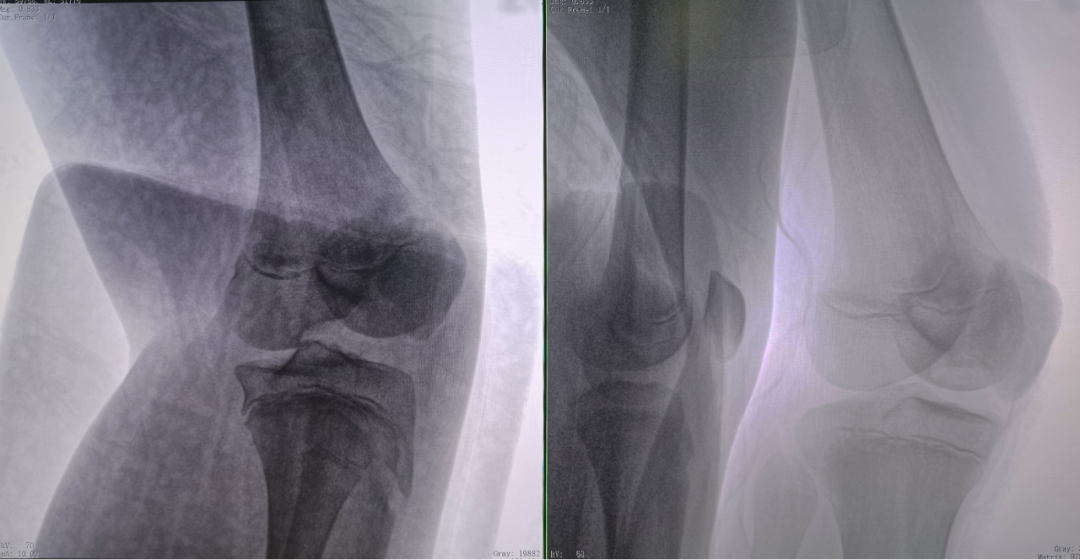

病例2 踝關(guān)節(jié)骨折復(fù)位(31歲)

在踝關(guān)節(jié)骨折復(fù)位手術(shù)中,用三維C可以更好地觀察骨折部位的復(fù)位情況:

正側(cè)位影像觀察脛腓聯(lián)合復(fù)位良好

從三維影像看,復(fù)位欠佳,貼合度不夠